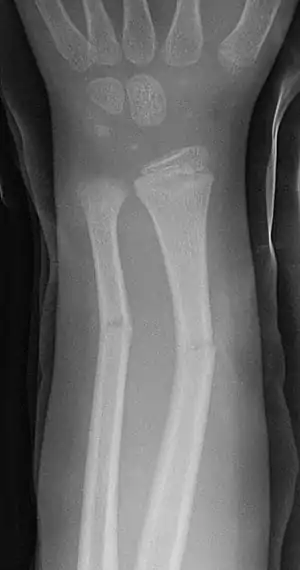

Greenstick fractures on X-ray.

Greenstick fractures

Projectional radiography is generally preferable.